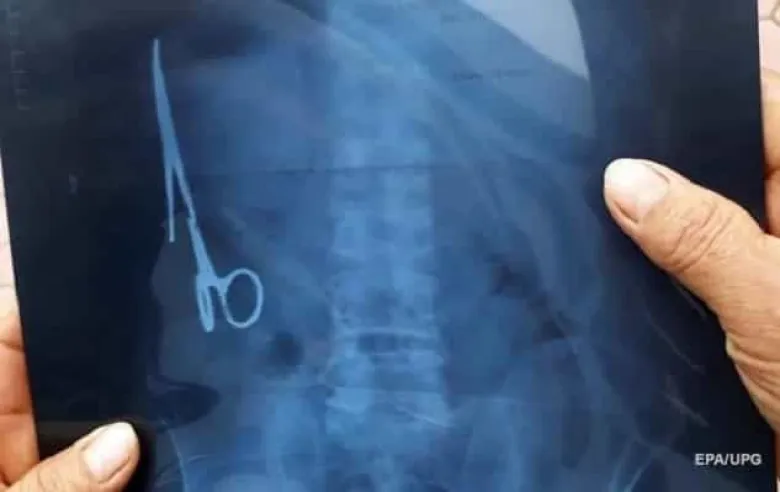

Ուկրաինայում քաղաքացին մկրատ է կուլ տվել

Ուկրաինայի Լվովի շրջանի բժշկական հաստատություններից մեկում մարդու մարմնից մկրատ են հանել:

Հաղորդվում է, որ հունիսի 18-ին քաղաքապետի հետ ամենշաբաթյա հավետվության ժամանակ տեղի մարզային հիվանդանոցի բժիշկը հայտնել է, որ բարդ վիրահատության միջոցով հաջողվել է մարդու մարմնից դուրս բերել մկրատը: Նշվում է, որ մկրատը կուլ տված քաղաքացին հոգեկան խնդիրներ է ունեցել:

Վիրահատությունից հետո բժիշկները նրա վիճակը գնահատել են կայուն: